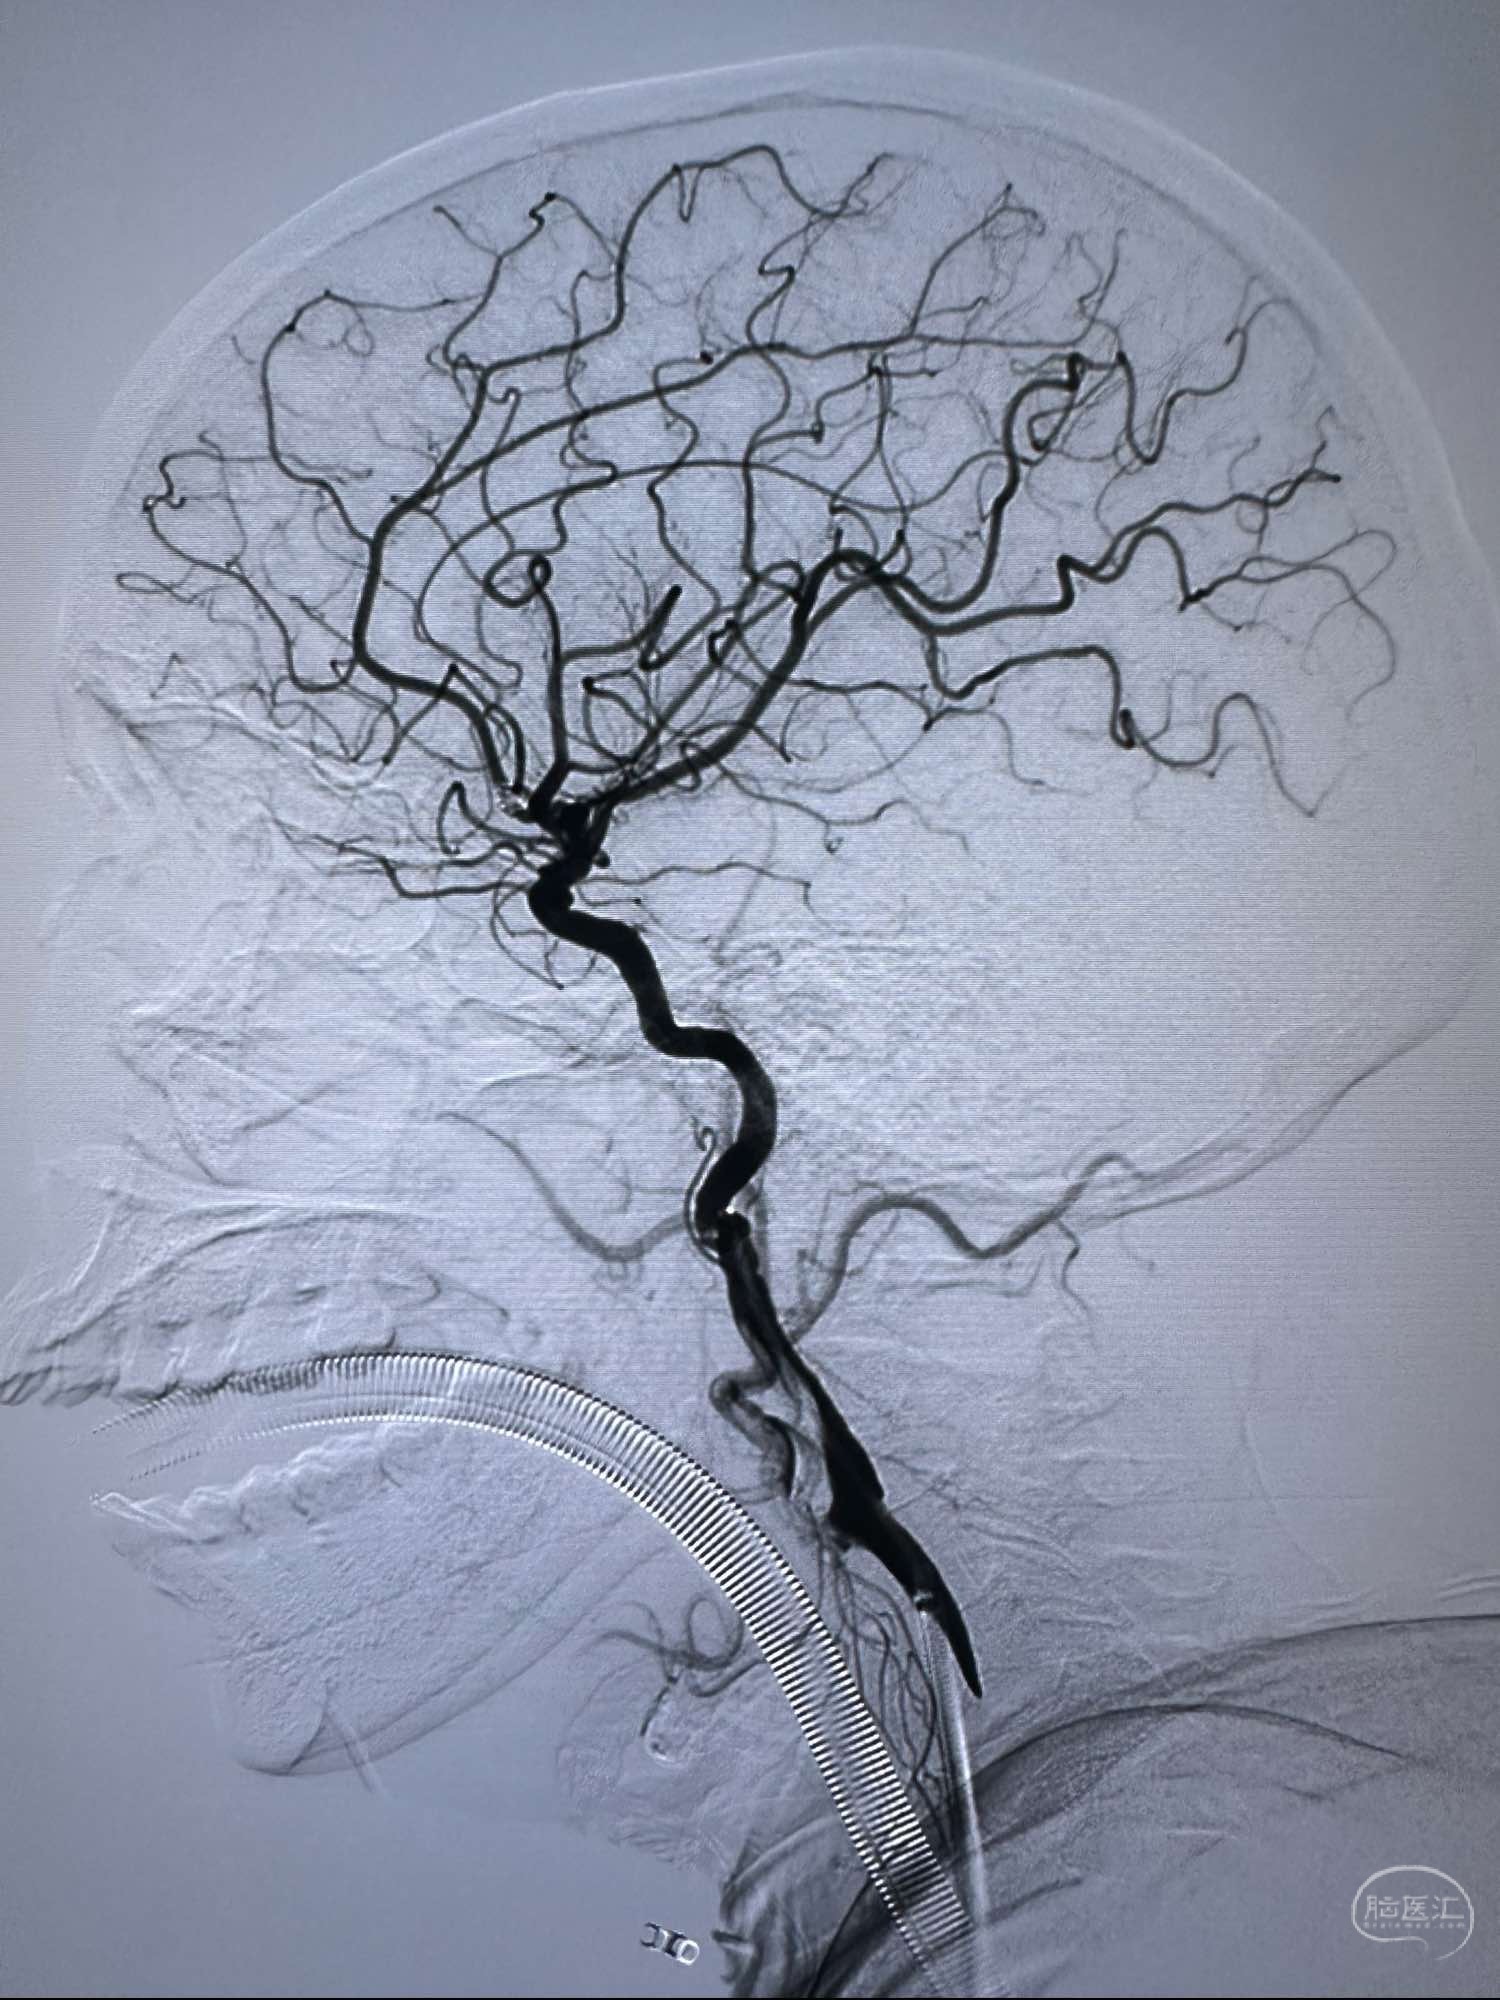

侧位

侧位